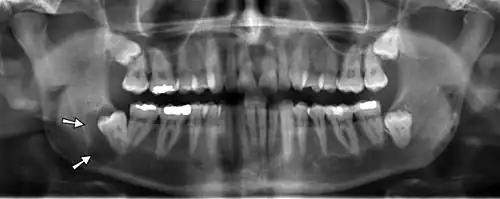

Panoramic radiographs have the capability to demonstrate a portion of the neck and display atheromas (calcifications in the carotid artery) which are an indication of both local and generalized (systemic) atherosclerosis. Atherosclerosis of the coronary arteries leading to myocardial infarction (heart attack), and atherosclerosis of the carotid artery leading to stroke are the number one and number three most common causes of death in the United States.[6]

There is interest to look at panoramic radiographs as a screening tool, however further data is needed with regards if it is able to make a meaningful difference in outcomes.[7]

Epidemiology: general public and high risk groups

Additional research projects have further determined the prevalence rate of these atheromas in the general population (3–5%)[8][9] and among high-risk groups (over 25% in: recent stroke victims,[10] individuals with obstructive sleep apnea syndrome,[11][12][13] postmenopausal women,[14] type 2 diabetics,[15][13][16] individuals with dilated cardiomyopathy,[17][13] and among individuals who have received radiotherapy directed at the neck,[18][19]). These findings have been corroborated by other several other researchers.[20][21][22][23][13]

Dental infection and atherosclerosis

Atherosclerosis is attributed to risk factors that include cigarette smoking, hyperlipidemia, obesity, diabetes mellitus, and hypertension (high blood pressure). These factors, however, do not fully account for the risk of disease. Atherosclerosis has been conceptualized as a chronic inflammatory response to endothelial cell injury[24] and dysfunction possibly arising from chronic dental infection. In 2010, using the previously validated Mattila panoramic radiographic index to quantify the totality of dental infection (i.e., periapical and furcal lesions, pericoronitis sites, carious tooth roots, teeth with pulpal caries, and vertical bony defects), Friedlander's group determined that individuals with carotid artery atheromas on their panoramic radiographs had significantly greater amounts of dental infection/inflammation than atherogenic risk-matched controls devoid of radiographic atheromas.[25][26] While the Mattila index had been previously used to relate the extent of dental infection to coronary artery disease, this research is the first to link the full range of dental disease that it measures to panoramic radiographs evidencing calcified carotid artery atherosclerosis.